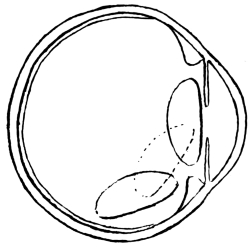

PLATE II.

FACING

PAGE

10.

LENS DISLOCATED BETWEEN CILIARY BODY AND SCLERA

curly bracket span

38

11.

NUCLEUS OF CATARACT FREELY MOVABLE BETWEEN THE AQUEOUS AND VITREOUS CHAMBERS

12.

LENS IMPACTED IN ANGLE OF ANTERIOR CHAMBER

13.

CAPSULE OF MORGAGNIAN CATARACT IMPACTED IN ANGLE OF ANTERIOR CHAMBER

14.

LENS FLOATING FREE IN VITREOUS CHAMBER

15.

LENS LIGHTLY IMPRISONED IN EXUDATE INTO VITREOUS CAVITY